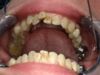

Das war der Zustand im September 2025.